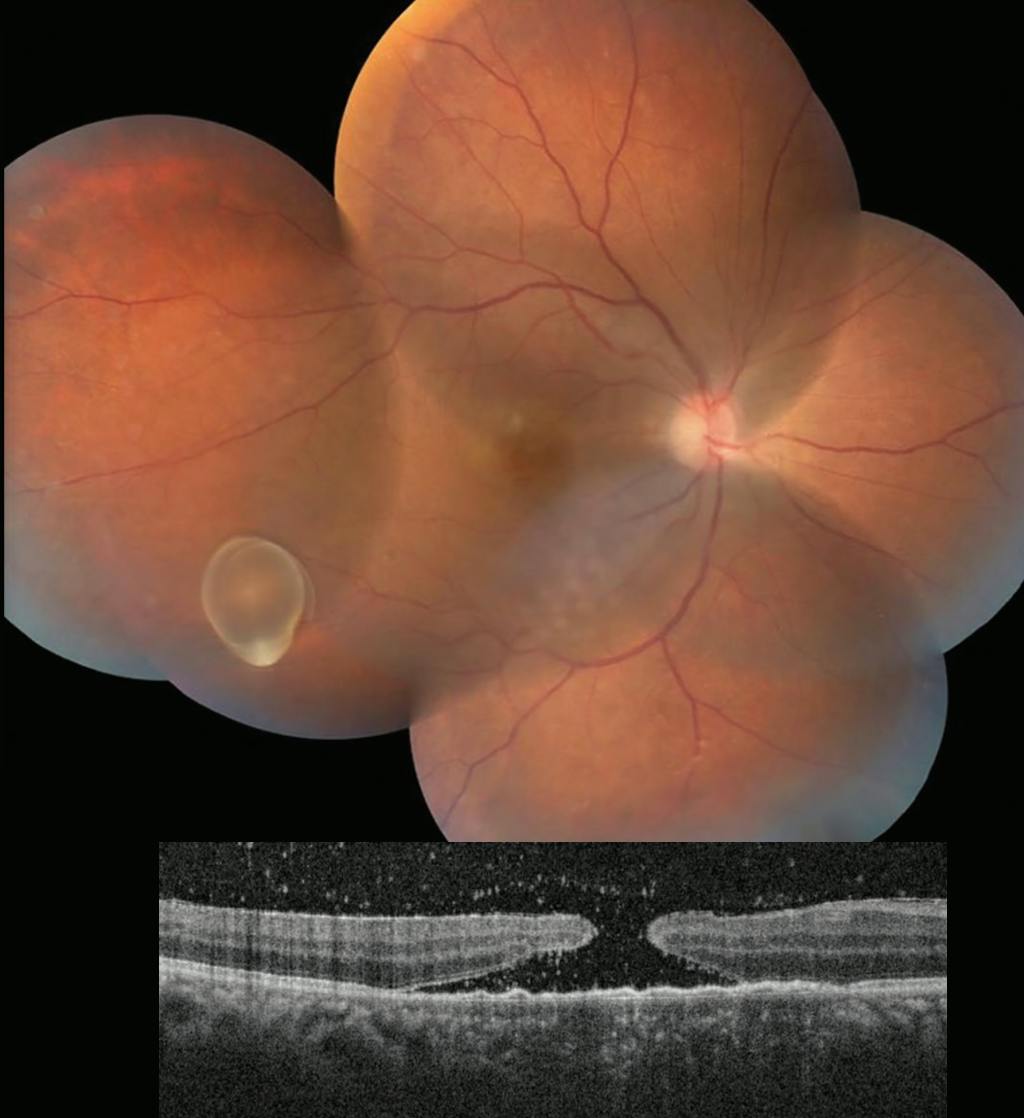

A 41-year-old man presented with diminution of vision in his right eye for 3 months. VA was 20/400 OD. On fundus examination, a solitary live intravitreal cysticercus cyst was noted (Figure 1, Top). Spectral-domain OCT showed a large full-thickness macular hole of 1,500 μm diameter with retinal pigment epithelium alterations at the macula (Figure 1, Bottom). The anterior segment examination was unremarkable. Neuroimaging showed no involvement of the central nervous system.

The patient underwent 23-gauge pars plana vitrectomy. Intraoperatively, the cyst was aspirated with the cutter (Figure 2, Top). To address the macular hole, inverted internal limiting membrane (ILM) peeling was performed under a bubble of perfluorocarbon liquid (PFCL; Figure 2, Middle).

Postoperatively, OCT revealed a type 1 closure of the macular hole (Figure 2, Bottom) and the absence of any inflammation. BCVA at final follow-up was 20/80 OD.